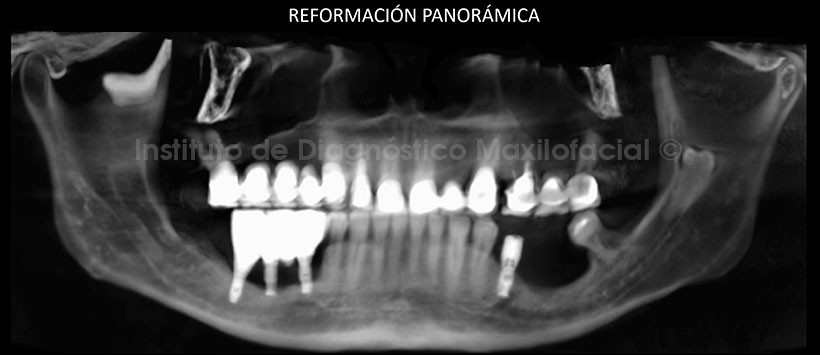

En la reformación panorámica obtenida mediante la tomografía volumétrica de haz cónico, se confirmó la presencia de esta pieza dentaria así mismo en los cortes transaxiales y tangenciales se pudo observar que se encuentra en una posición equidistante en relación a ambas tablas óseas. También se pudo evidenciar que esta pieza se encuentra próxima a la cortical superior del conducto dentario inferior.

En las reconstrucciones 3D se pueden apreciar la ubicación exacta de la pieza retenida y su relación con las estructuras óseas adyacentes.